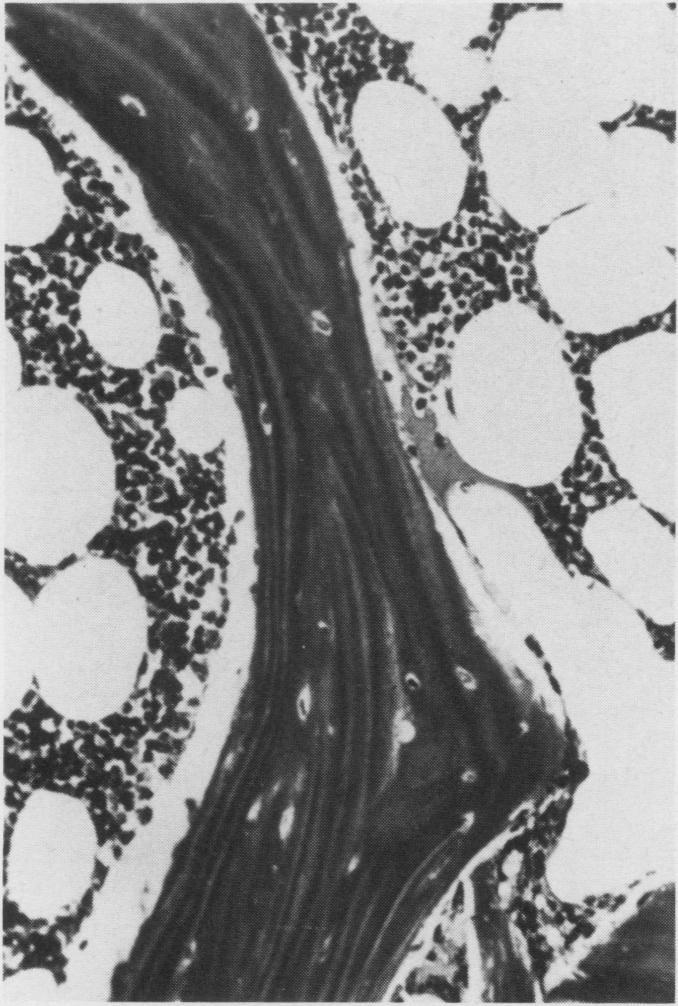

Necrosis of intramedullary bone and bone marrow elements is reported in the long bones of a dog. Radiographically lesions were evident as an irregular increase in intramedullary density. On gross postmortem examination necrotic tissue appeared as yellow-white deposits on the endosteal surface and in the medullary cavity. Microscopically, necrotic bone had empty lacunae and was often covered by basophilic, woven bone. The cause and pathogenesisof aseptic necrosis of bone are discussed.